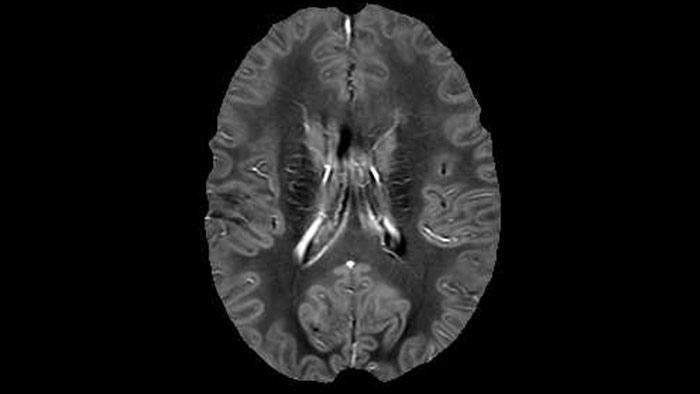

QSM based on a Compressed SENSE multi-echo SWI.

He says the accelerated scanning is achieved via the use of Compressed SENSE and MultiBand SENSE. “We can use Compressed SENSE acceleration factors of about 10 on a 3D FLAIR for instance, which is quite remarkable compared with what we saw with the Achieva. With 3D FLAIR, we can push the spatial resolution to 0.3 cubic mm and it works. Previously, our 3D FLAIR scans lasted about 8 minutes, but now with Elition they are five minutes. The SNR is also visibly better. Our SWI and QSM scans look fantastic. Also, since a lot of neuroimaging is EPI based, using the MultiBand SENSE technique can increase temporal resolution and make it possible to run complicated DTI scans relatively quickly.”

Dr. Rauscher says, “With better gradients we can use a shorter echo spacing on the spin echo, so we get better sampling of the rapidly decaying myelin signal, which typically has T2 of around 10-20 milliseconds at 3 Tesla. If we can reduce echo spacing from about 8 to 5-6 milliseconds, we get a much better sampling of the short decay component and increase our SNR, which is a big advantage. The same is true for multi-echo gradient echo which we use for susceptibility mapping and for mapping venous vessels in MS.”